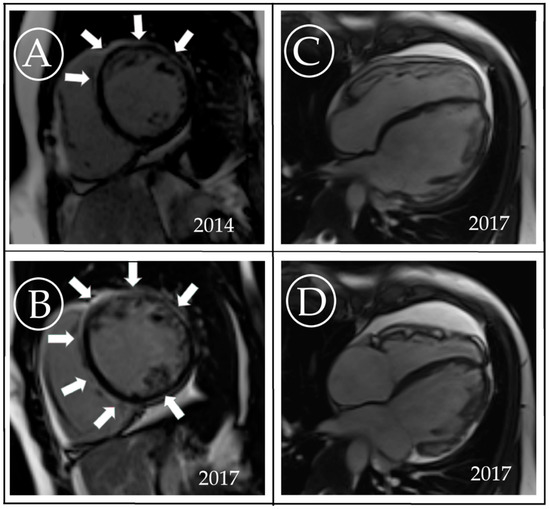

3. Case Description